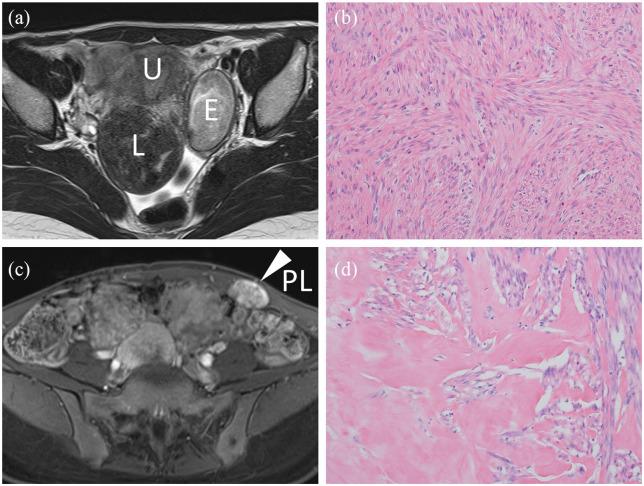

Although parasitic leiomyoma could be spontaneous or iatrogenic in origin, port-site implantation of parasitic leiomyoma is an iatrogenic benign sequela of laparoscopic surgery. A 30-year-old, primigravida Japanese woman was referred after unresponsiveness to preoperative gonadotropin-releasing hormone for intramural fibroids. Magnetic resonance imaging showed multiple intramural fibroids and left ovarian endometrioma with no malignant features. Laparoscopic myomectomy with power morcellation and ovarian cystectomy were performed, followed by treatment with a combined oral contraceptive. Seven years after the primary surgery, she underwent abdominal myomectomy for a port-site, and peritoneal recurrence of the leiomyoma and intramural leiomyomas was detected. Microscopic examination revealed that resected specimens from the port-site demonstrated leiomyoma with lesser cell density and more prominent hyalinization than those from the uterus. Therefore, clinicians should counsel patients regarding the risks and benefits of laparoscopy with morcellation versus laparotomy. Further development of techniques for uterine tissues extraction is warranted.

尽管寄生性平滑肌瘤的起源可能是自发的或医源性的,但寄生性平滑肌瘤的穿刺孔植入是腹腔镜手术的一种医源性良性后遗症。一名30岁的初产妇日本女性因术前使用促性腺激素释放激素治疗壁间肌瘤无效而前来就诊。磁共振成像显示多个壁间肌瘤和左侧卵巢子宫内膜瘤,无恶性特征。进行了腹腔镜子宫肌瘤切除术和电动粉碎术以及卵巢囊肿切除术,随后使用复方口服避孕药进行治疗。初次手术后七年,她因穿刺孔处的肌瘤接受了腹部子宫肌瘤切除术,并检测到平滑肌瘤和壁间肌瘤的腹膜复发。显微镜检查显示,穿刺孔处切除的标本显示平滑肌瘤的细胞密度低于子宫标本,玻璃样变更明显。因此,临床医生应就腹腔镜粉碎术与开腹手术的风险和益处向患者提供咨询。子宫组织提取技术的进一步发展是必要的。